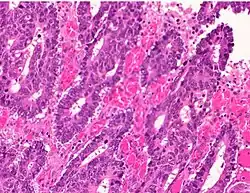

Adenocarcinoma is a malignant epithelial tumor, originating from superficial glandular epithelial cells lining the colon and rectum. It invades the wall, infiltrating the muscularis mucosae layer, the submucosa, and then the muscularis propria. Tumor cells describe irregular tubular structures, harboring pluristratification, multiple lumens, reduced stroma ("back to back" aspect). Sometimes, tumor cells are discohesive and secrete mucus, which invades the interstitium producing large pools of mucus. This occurs in mucinous adenocarcinoma, in which cells are poorly differentiated. If the mucus remains inside the tumor cell, it pushes the nucleus at the periphery, this occurs in "signet-ring cell." Depending on glandular architecture, cellular pleomorphism, and mucosecretion of the predominant pattern, adenocarcinoma may present three degrees of differentiation: well, moderately, and poorly differentiated.[5]

- Invasive adenocarcinoma commonly displays:[6]

- Varying degrees of gland formation with tall columnar cells

- Frequently desmoplasia

- Dirty necrosis, consisting of extensive central necrosis with granular eosinophilic karyorrhectic cell detritus.[6][7] It is located within the glandular lumina,[7] or often with a garland of cribriform glands in their vicinity.[6]